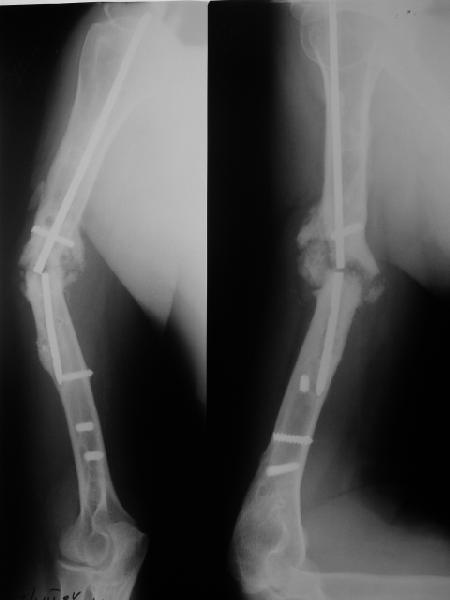

Наверно, можно пойти на укорочение, убрав металлический цилиндр, не такой уж большой дефект. Снимки в чем-то похожего пациента прилагаю - тоже несращение диафиза после многократных операций, и надмыщелковый свежий перелом (случился после удаления обломка стержня аппарата).